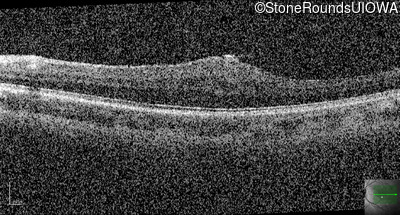

This 9 year old male was noted to have some crossing of his eyes at 2 months of age and the eye exam which followed identified a retinal lesion in the right eye. When he was six years old an epiretinal membrane was noted in his left eye. Two years later it was decided that it was a thin hamartoma in that eye as well. He underwent neuroimaging at age 7 which identified bilateral acoustic neuromas.